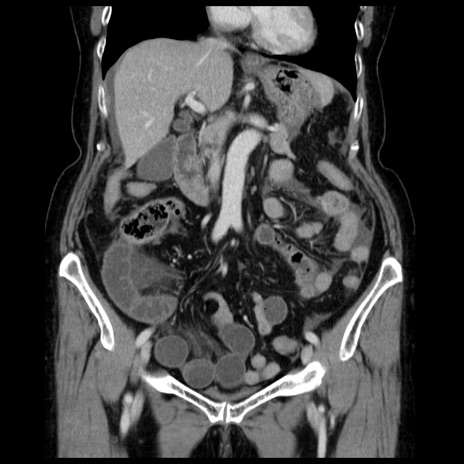

症例13(冠状断像)

【症例】70歳代女性

【主訴】腹痛、嘔吐

【現病歴】15時間程前(昨晩)より腹痛あり。今朝になっても症状の改善なく、嘔吐あり。腹痛も増悪あり、救急外来受診。

【既往歴】子宮癌全摘術後

【身体所見】意識清明、BP 121/72mmHg、P 74bpm、SpO2 100%(RA)、腹部:平坦・軟、腸雑音ほぼ聴取せず。下腹部・心窩部・臍左上に圧痛あり。反跳痛なし。

【データ】WBC 10600、CRP 0.15

横断像